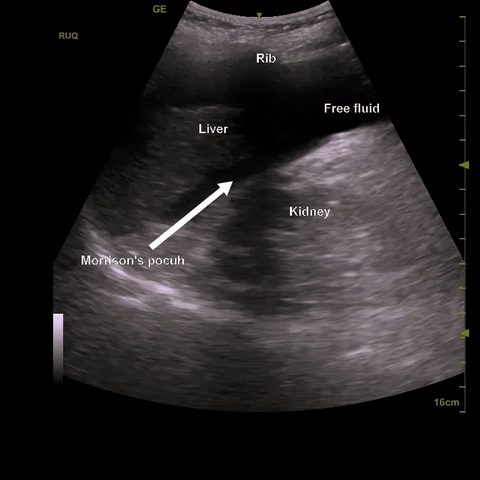

We use the same approach as the Focused Assessment with Sonography in Trauma (FAST) exam imaging the right upper quadrant (RUQ), left upper quadrant (LLQ), and pelvis in a systematic fashion. A positive scan is the presence of anechoic material that has irregular margins and settles into gravity dependent regions of the peritoneum in any of these views.

RUQ: Locate the xiphoid process and move laterally to the right mid axillary line or even the posterior axillary line over the ribs with the probe in the longitudinal orientation. Identify the liver and kidney and the interface between them, the hepatorenal interface or Morrison’s pouch. Fan anterior to posterior through the whole space looking for anechoic material. Be sure to interrogate the whole of Morrison’s pouch, the sub-diaphragmatic space and the caudal tip of the liver by fanning anterior to posterior through each of these structures. Fluid in any of these areas constitutes a positive scan.

Caudal tip of the liver: The most sensitive point for detecting free fluid in the RUQ is the caudal tip of the liver.